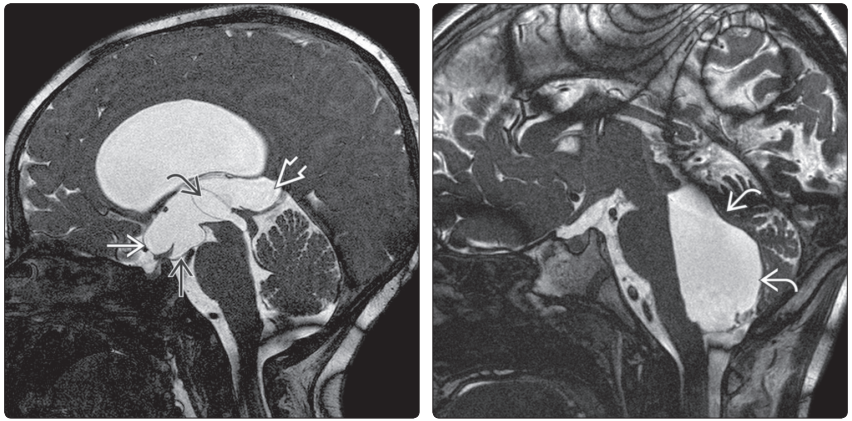

(左图)矢状位自由稳态进动序列(FIESTA)示:脑室内囊肿↪阻塞中脑导水管,导致侧脑室和第三脑室显著扩张。视交叉隐窝→显著扩张,第三脑室底→和松果体上隐窝⇒受压下凸。(右图)矢状位(FIESTA)示:中脑导水管狭窄引起第四脑室不成比例的显著扩张↪,侧脑室、第三脑室受压

(左图)横断位FLAIRMRI示:侧脑室扩张伴间质水肿→。(右图)MR矢状位T2WI示:由第四脑室流出孔和基底池瘢痕(早产儿大面积脑室出血)导致的严重脑积水。双侧脑室显著扩张,导致胼胝体上抬、变长。第三脑室隐窝扩张,导水管狭窄引起的流空现象↪,第四脑室经Magendie孔突出于小脑蚓部下方→